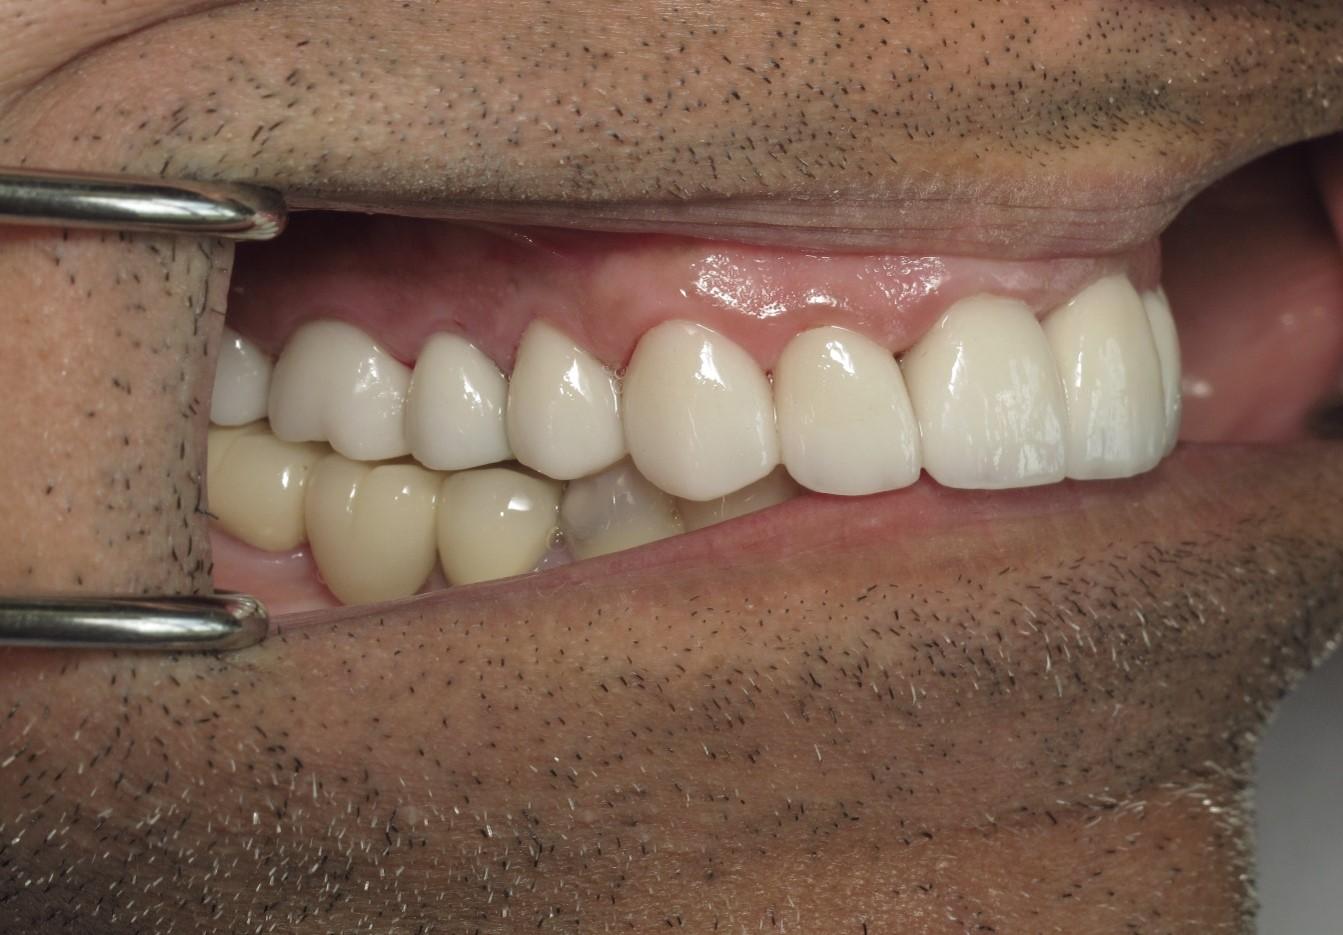

https://demo.discussdentistry.com/forums/topic/no-prep-veneers/#post-26022 <![CDATA[No prep veneers]]> https://demo.discussdentistry.com/forums/topic/no-prep-veneers/#post-26022 Mon, 15 Apr 2024 03:43:21 +0000 Amit Kumar The patient is a successful physician who desired an improved smile but did not want to “shave down” his teeth.

No prep veneers were delivered from the upper second bi-cuspid to the second bi-cuspid on the contra-lateral side.  No temporaries were needed.

The patient also wanted to include his lower anterior teeth, however,Pre opPre op right sidePre op left sideTry in right sideTry in left sideFinal 1Final 2 there was not enough clearance to accomplish this using no-prep technique.

You can note that the upper central was lengthened by 20%.